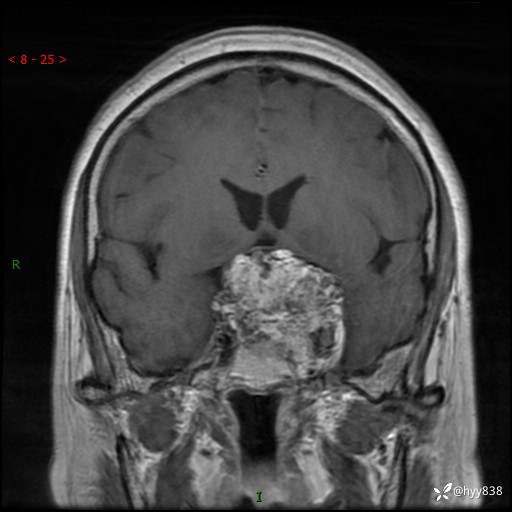

鞍区MRI平扫

增强 COR +SAG